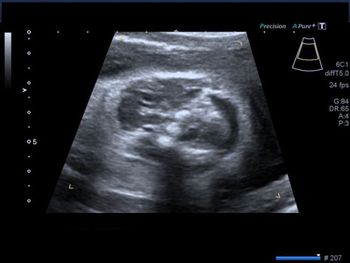

What's your diagnosis based on these images of the fetal neck?